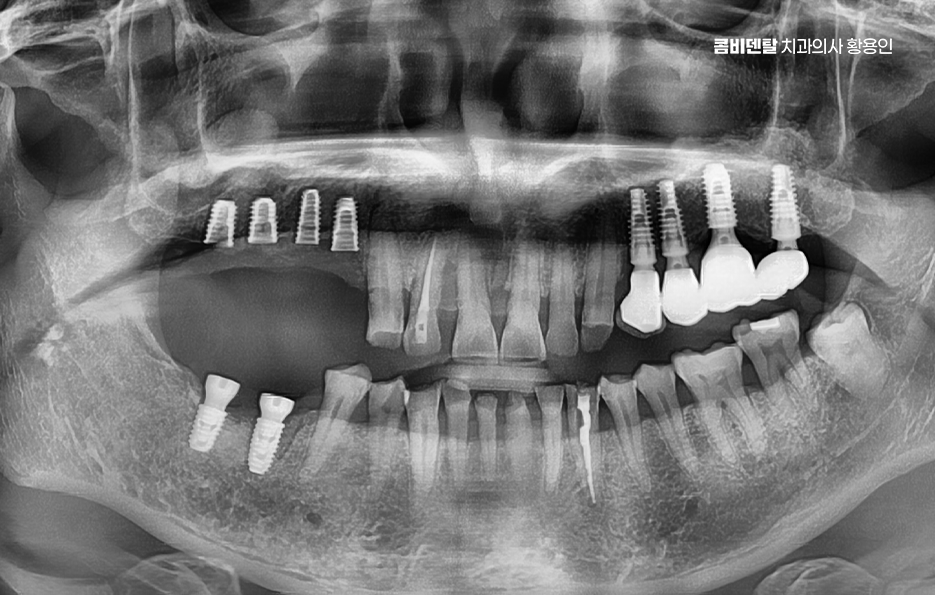

어금니 임플란트 과정은 정밀 진단에서 시작되며 잇몸뼈 안에 인공 치근을 심는 방식이기 때문에 뼈 상태 확인이 필수적으로 파노라마 촬영이나 3차원 CT를 통해 뼈 높이와 폭, 신경 위치를 확인하고 특히 아래 어금니는 하치조신경과 가까워서 정확한 위치 파악이 중요하며 위 어금니는 상악동과의 거리도 고려해야 할 필요가 있어요

임플란트를 심을 잇몸 뼈가 충분하다면 바로 식립이 가능하지만 치아를 빼고 오래 방치한 경우에는 뼈가 흡수되어 부족할 수 있으며 이때는 뼈이식을 먼저 하거나 동시에 진행하고 어금니는 씹는 힘이 강하기 때문에 초기 고정이 단단해야 하며 유지까지 고려할 때 교합의 정교한 맞물림이 중요한 부위라고 할 수 있었어요

어금니 임플란트 과정에서 수술 당일에는 국소마취 후 잇몸을 절개하거나 최소 절개로 접근해 뼈에 임플란트를 식립하며 수술 후에는 일정 기간 골유착을 기다리는데 임플란트와 뼈가 단단히 결합하는 과정이라 할 수 있었어요

골유착이 완료되면 지대주를 연결하고 본을 떠서 최종 보철물을 제작하며 어금니 크라운은 강도와 교합 조화를 동시에 고려해 제작하는데 씹는 힘이 집중되는 부위이기 때문에 높이와 접촉점 조정이 중요하며 교합이 맞지 않으면 나사가 풀리거나 보철물에 문제가 생길 수 있어서 장착 후에도 교합 점검 및 정기적인 검진, 스케일링 등의 관리가 중요할 수 있어요